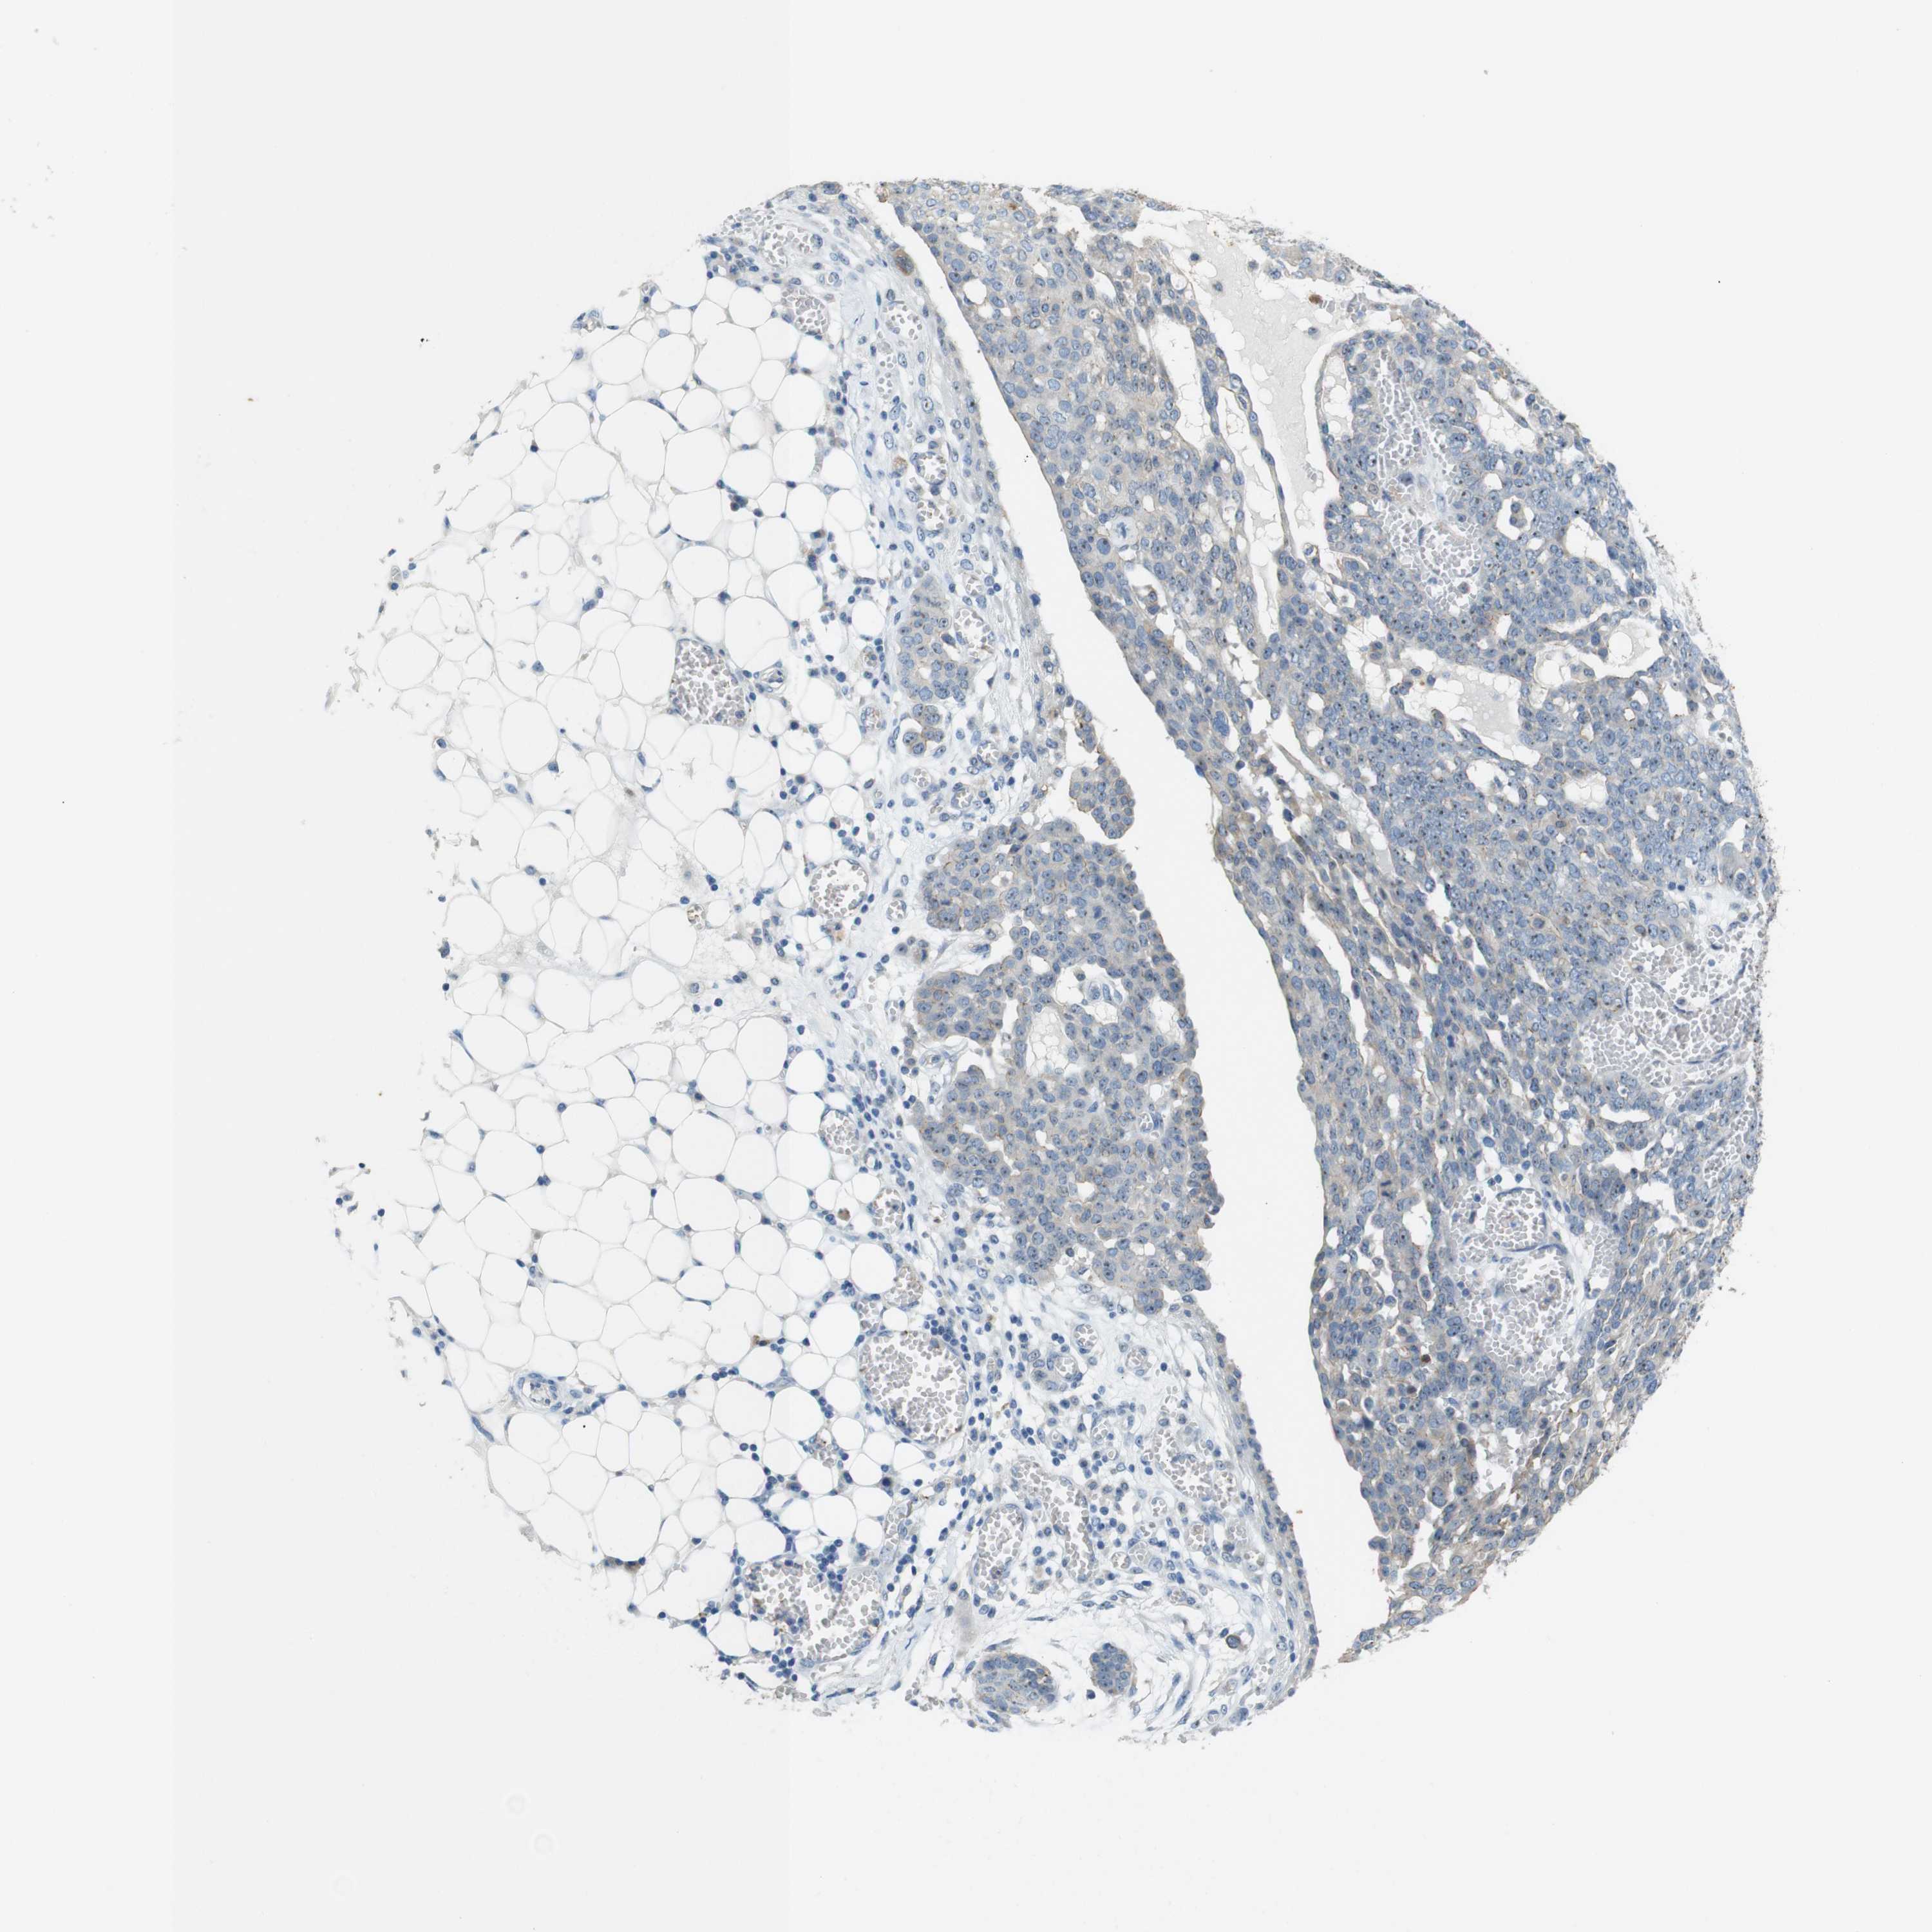

OVARIAN CANCER - Protein expressioni

A mouse-over function shows sample information and annotation data. Click on an image to view it in a full screen mode. Samples can be filtered based on level of antibody staining by selecting one or several of the following categories: high, medium, low and not detected. The assay and annotation is described here.

Note that samples used for immunohistochemistry by the Human Protein Atlas do not correspond to samples in the TCGA dataset.

Antibody stainingi

Antibody staining in the annotated cell types in the current human tissue is reported as not detected, low, medium, or high, based on conventional immunohistochemistry profiling in selected tissues. This score is based on the combination of the staining intensity and fraction of stained cells.

Each image is clickable and will lead to virtual microscopy that enables deeper exploration of all samples and also displays staining intensity scores, fraction scores and subcellular localization as well as patient and tissue information for each sample.

Antibody HPA053337

Antibody CAB013244

Cystadenocarcinoma, serous, NOS